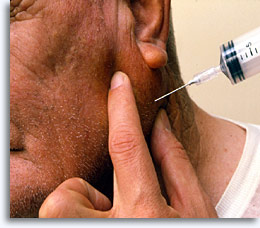

Fijne naald aspiratiebiopsie is een veilige en doeltreffende methode om cellen te verkrijgen voor diagnostische cytologische beoordeling van palpabele oppervlakkige massa’s van borst, schildklier, speekselklieren, lymfknopen, cysten en metastatische tumoren, met behulp van een 20 cc injectiespuit, 22 gauge naald en een optionele injectiespuithouder [“gun”].

Na palpatie en antiseptische behandeling wordt de naald in het doelgebied ingebracht, de plunjer wordt teruggetrokken om onderdruk te creëren terwijl de naald een paar keer in verschillende richtingen heen en weer wordt bewogen. Wacht tot het evenwicht weer wordt bereikt en trek de naald uit de patiënt. De procedure is klaar als de aspirator vindt dat er voldoende penetratie is bereikt of er materiaal in de injectiespuit verschijnt. De injectiespuit wordt dan van de naald verwijderd en wordt gevuld met lucht die kan gebruiken om de naald weer leeg te spuiten. De injectiespuit kan met de hand vastgehouden worden of in een spuithouder geplaatst worden.